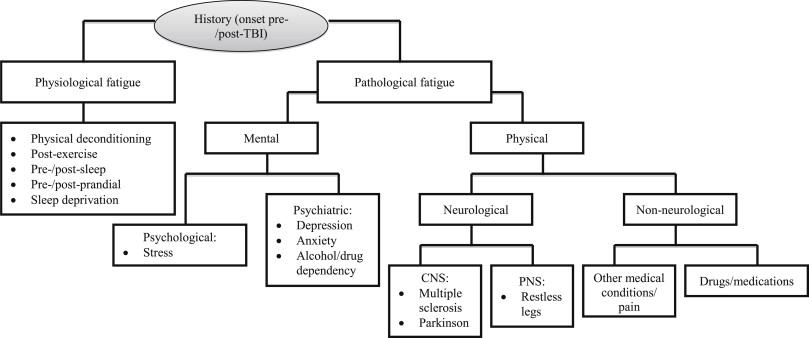

7) Apnea

Untreated sleep apnea causes daytime tiredness, even with a full night’s sleep

7e) Neurological Effects of Apnea

Emerging science can help explain the link between excessive daytime sleepiness (EDS) and OSA

- EDS is one of the most common symptoms of obstructive sleep apnea (OSA)